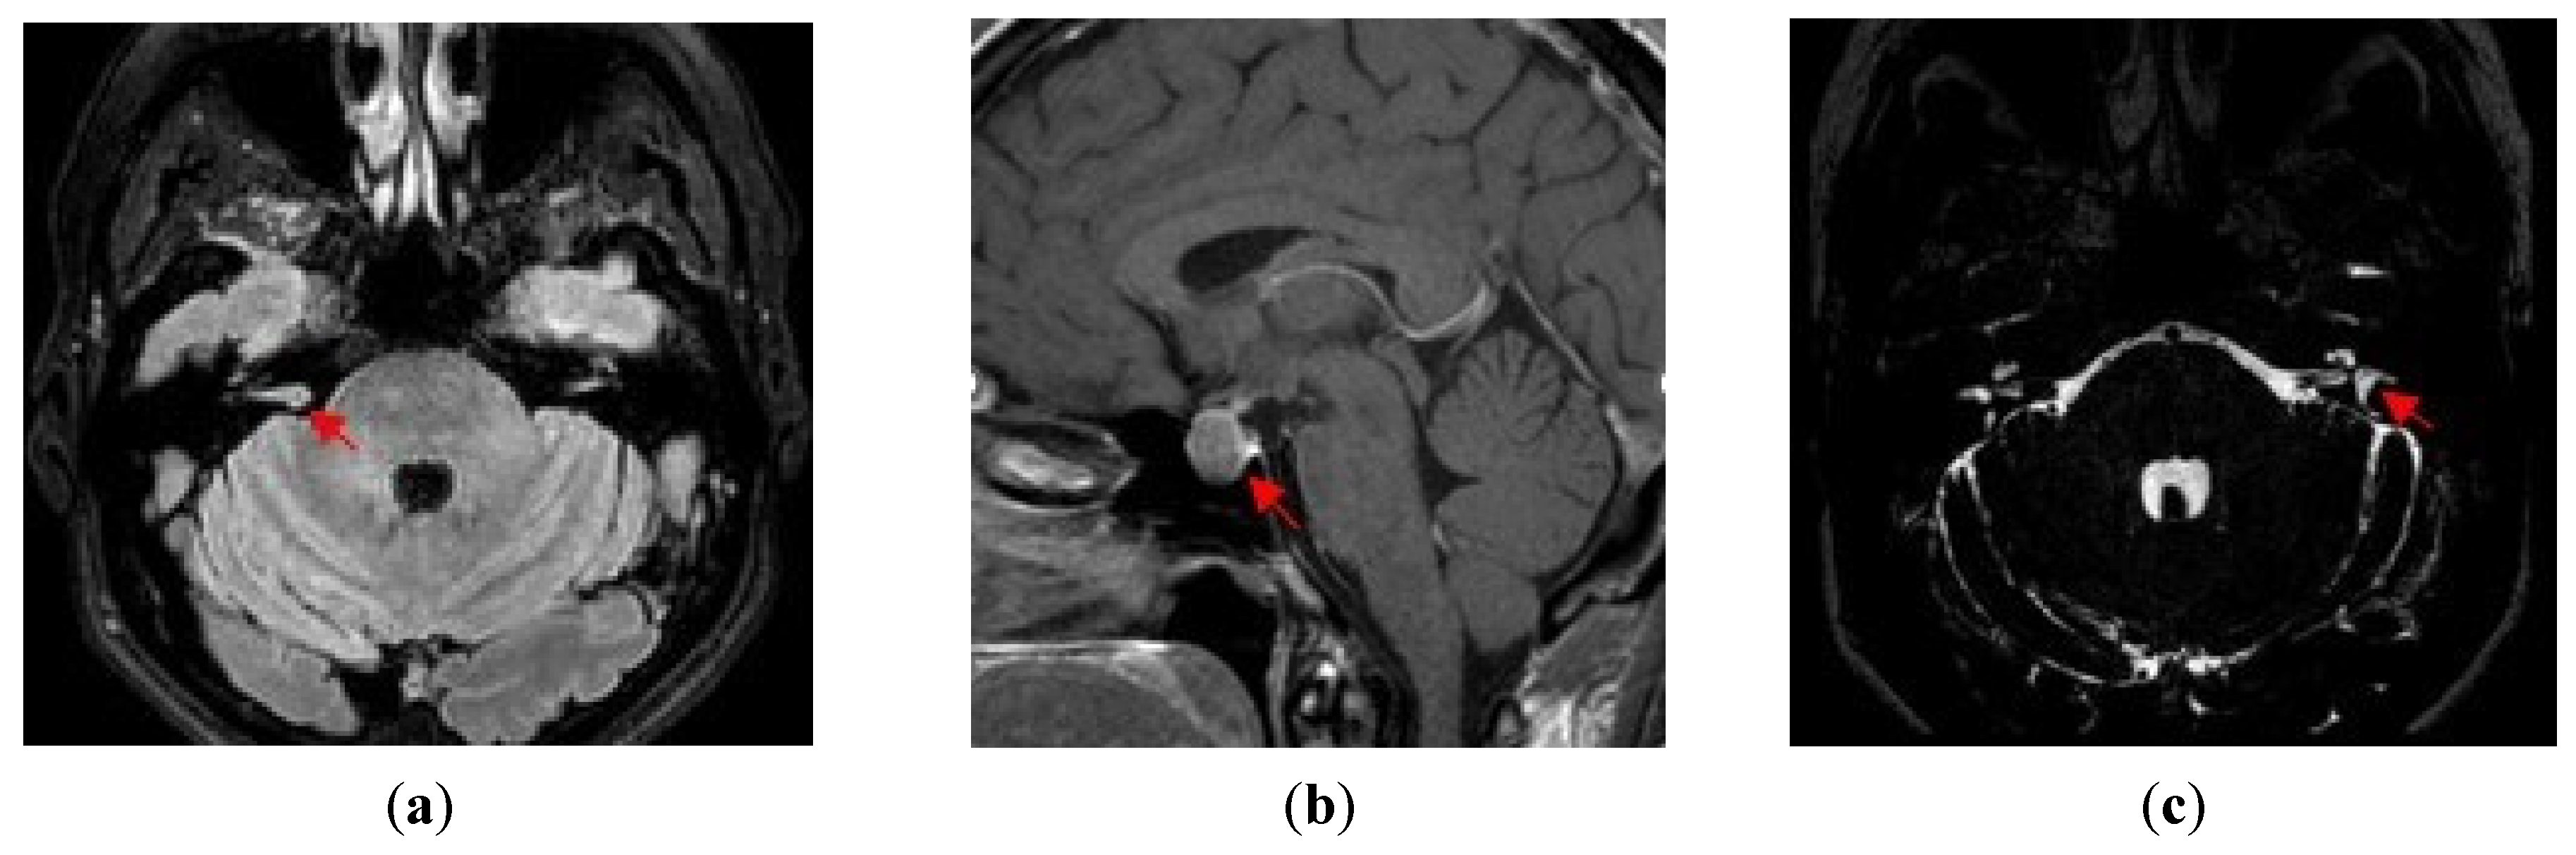

- (b)

- Growth hormone-secreting macroadenoma of the pituitary gland: chronic headache, hyperhidrosis, amenorrhea, insomnia, broadened hands and feet, widened and stubby fingers, and MRI findings;